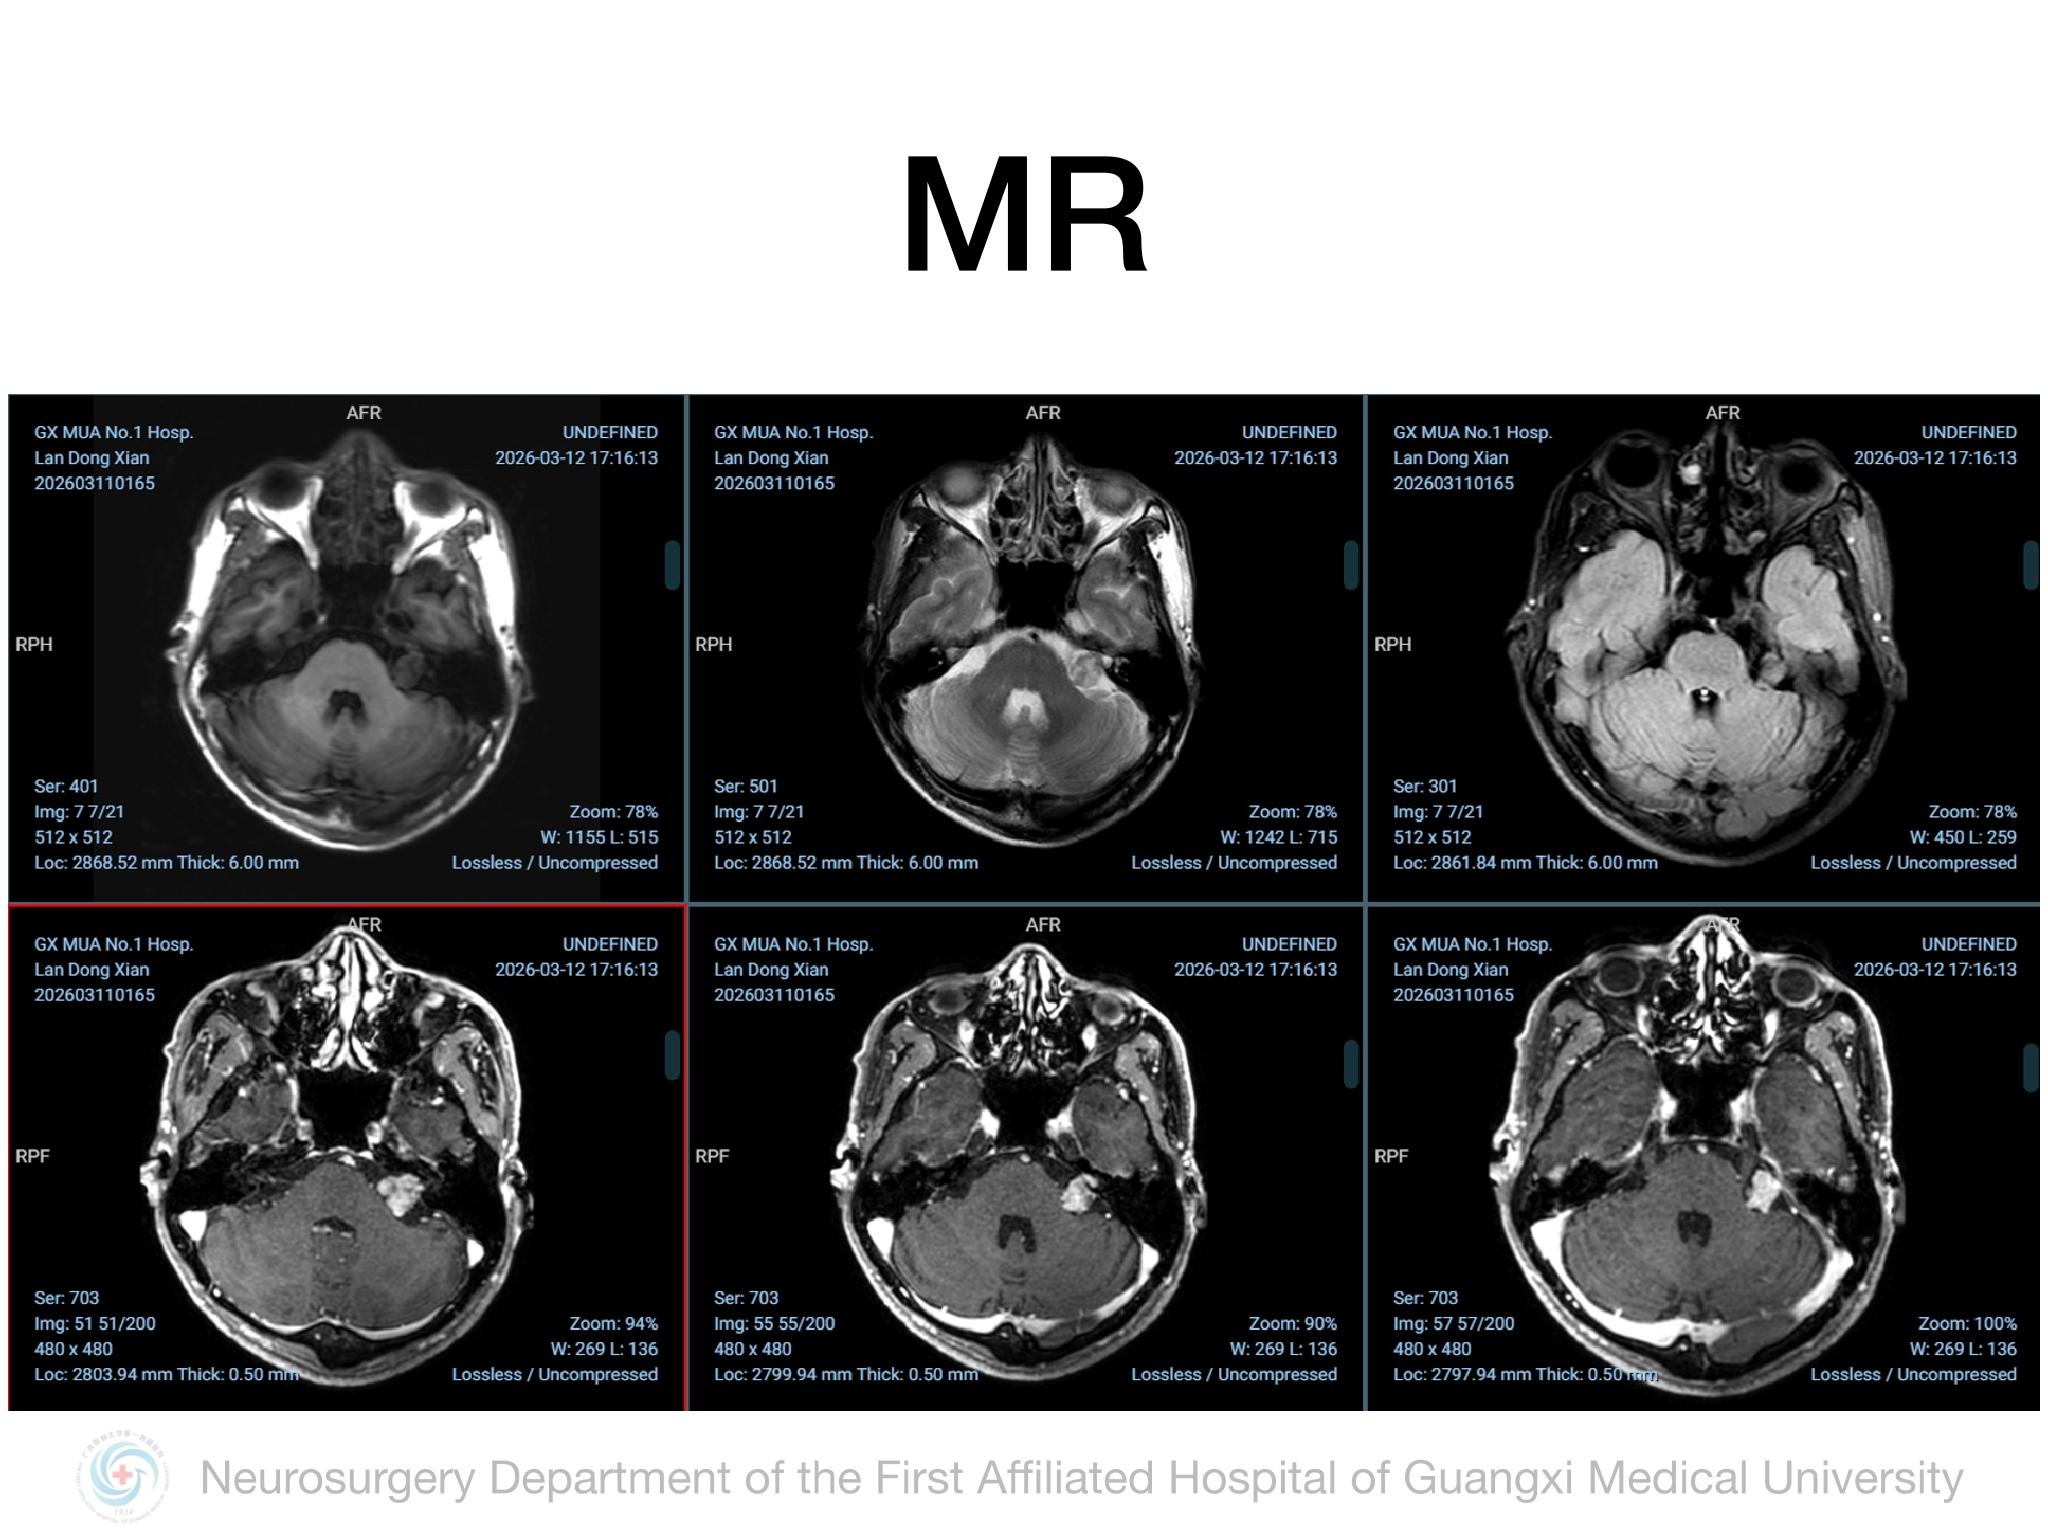

乙状窦后入路切除Koos3级听神经瘤

脑肿瘤-神经鞘瘤